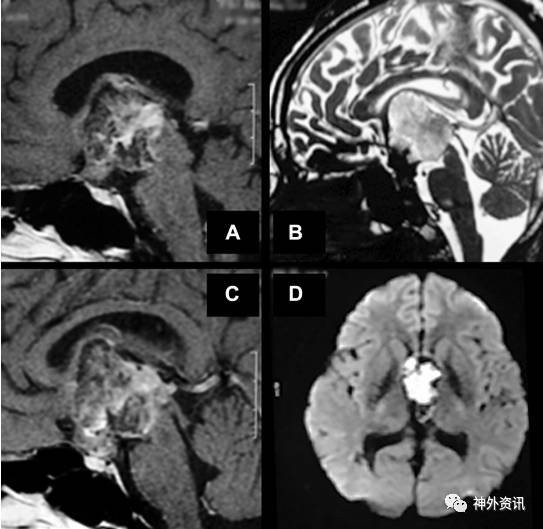

50岁女性患者,2年前因进行性头痛伴恶心呕吐入院。当时头颅MRI成像显示鞍区占位侵及三脑室,合并脑积水;术前考虑为颅咽管瘤(图1)。行脑室-腹腔分流手术。患者脑积水症状缓解。

图1. 首次入院的颅脑MRI成像。